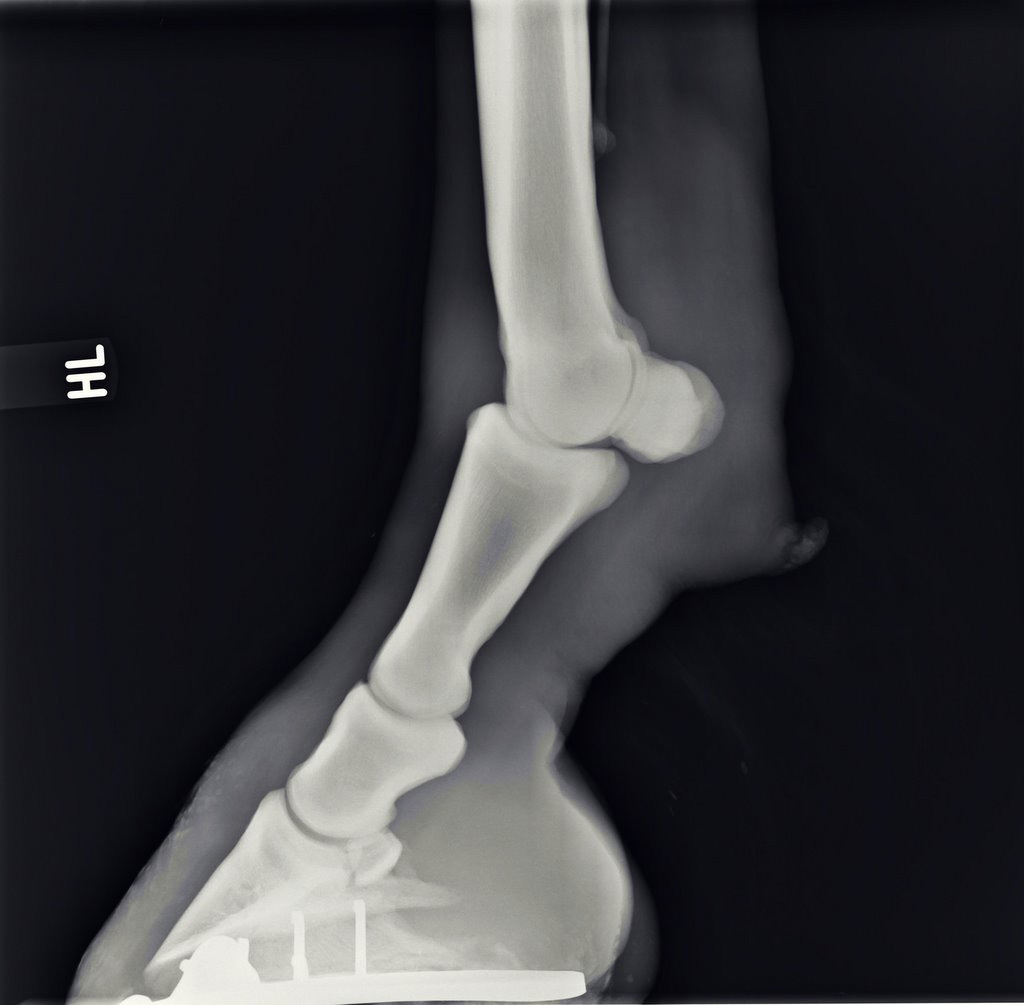

Illustrative Mindeststandardaufnahmen zur Beurteilung nach dem Röntgenleitfaden: